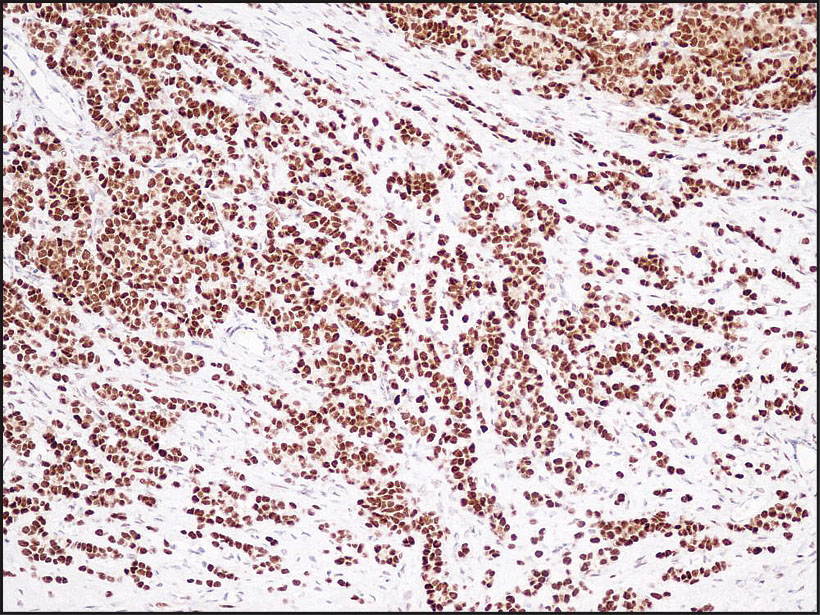

Anti-ER (Estrogen receptor)

Rabbit clonal antibody

IHC-P, dilution 1:100

Gallery

db053